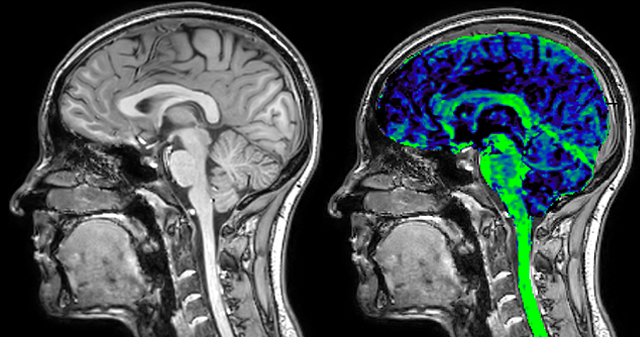

of limiting MWI to the brain, even without the cerebellum, we can now spend about the same amount of time and scan the whole brain and the cervical spinal cord, which is a huge boost for us.” Dr. Rauscher says, “For MWI we perform 3D T2 with 32 or more echoes. This used to take a long time, but with Compressed SENSE we can decrease this to ten minutes for the whole head. Because of the large field of view (FOV) on the readout direction, we even get information from the brainstem, which we previously missed when we were using the GRASE approach. Having the whole head scan is nice because it has spatial resolution, orientation and FOV that are comparable to the standard 3D clinical MS scans, including the FLAIR and 3D T2, and a 3D T1 for brain volume.”

T1 - Weighted, Myelin Water Fraction Superimposed

Spinal cord coverage

Smaller, more isotropic voxels

Excellent detail in quantitative maps

Images courtesy of Adam Dvorak, Department of Physics and Astronomy, University of British Columbia